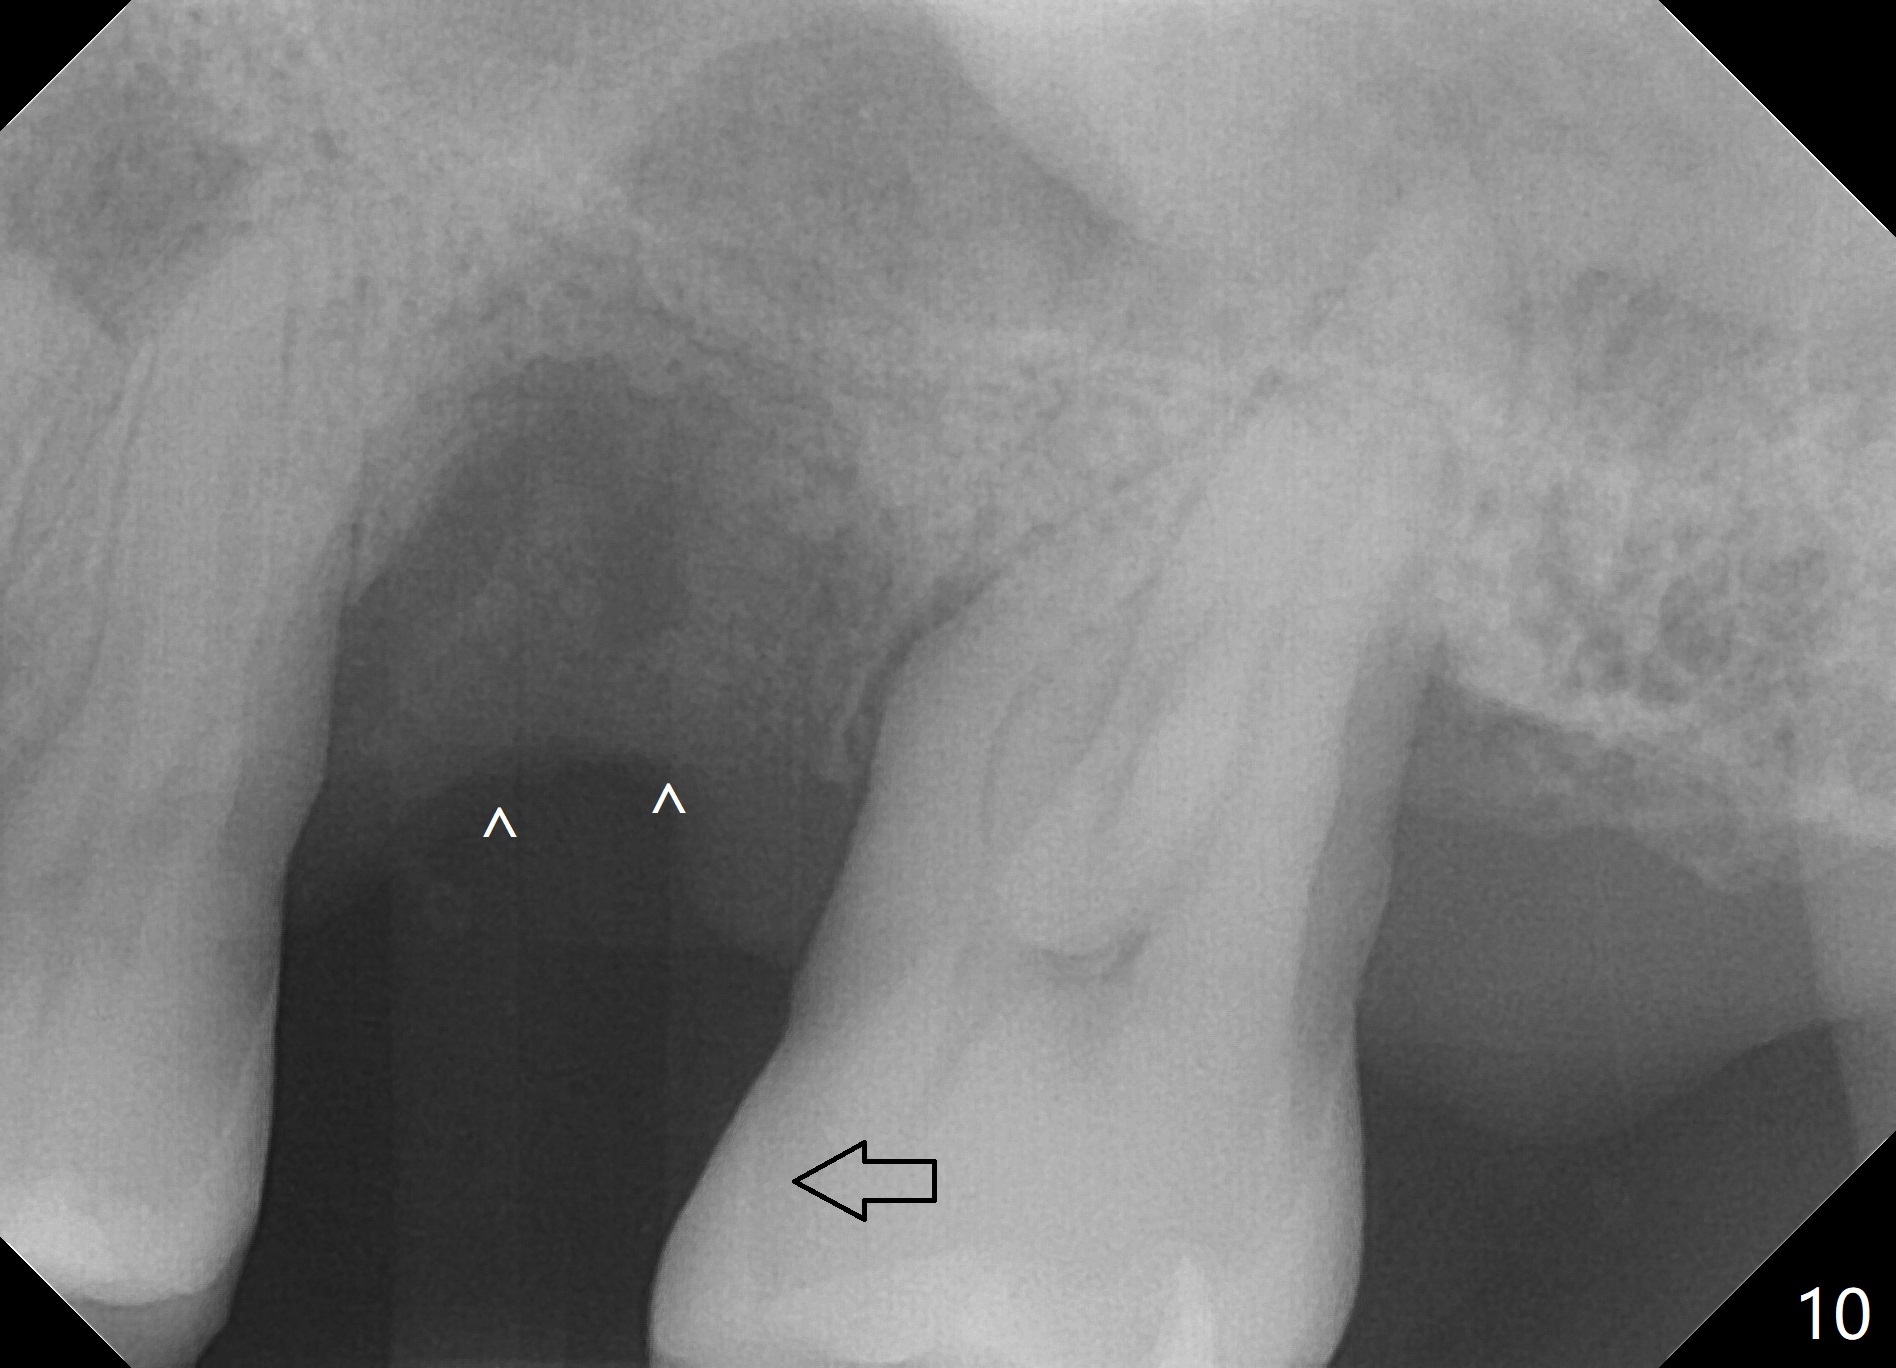

When the tooth #14 is extracted, the buccal plate is lost, while the apex of the palatal socket is perforated.  The palatal slope of the septum appears to be a suitable site for osteotomy, but the depth seems to be 2 mm.  After sequential osteotomy until 5.3 mm with drills, a 5.9 mm SM tap obtains stability (Fig.2).  A 5.9x8 mmm implant is placed with barely sufficient stability after 1 piece of PRF membrane and VeraGraft (Fig.2-4).  The implant rotates and dislodges when an abutment is being placed.  Neither do 6-8x17 mm Tatum taps achieve primary stability.  Socket preservation is performed, followed by periodontal dressing (Fig.5).  Primary stability might have been obtained if a smaller IBS implant with fins were placed in the palatal socket.  The periodontal dressing has dislodged 1 week postop; the socket appears healing (Fig.6,7).  Bone graft seems to be minimal or bone density of the graft is low (Fig.8).  The socket heals with a wide ridge 2 months post socket preservation, but the tooth #15 seems to be buccal (Fig.9) and mesial (Fig.10) shift.  After use of Magic Split and Expanders (until 3.8 mm for 13 mm), try 5 mm dummy implant (Fig.11).  If 6 mm one fails to achieve stability substantially, switch to 7 mm Tatum tapered tap provided there is enough mesiodistal space (use 8 mm implant positioner to gauze the space beforehand (preop)).  Consider using Vanilla (not Vera) Graft to fill in the gap between implant and osteotomy.  When primary stability is obtained, place a nonfunctional provisional to prevent further shifting (Fig.11 white outline).  After osteointegration, use the provisional (reline and separator) to distalize the tooth #15.